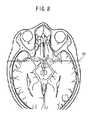

FIG. 10 is a diagram showing by way of example an anatomical tomographic image and names of living tissues, which are displayed according to the second embodiment.

Then, in step S57, the standardtomographic image identifier20 identifies from the three-dimensional standard image acquired in step S52 a standard tomographic image corresponding to the medical tomographic image corrected in step S56. At this time, the standardtomographic image identifier20 identifies a standard tomographic image, which is in conformity with the medical tomographic image at a level higher than a predetermined value, and which is in closest conformity with the medical tomographic image, according to the positioning process referred to above. The location (position) of the section within the three-dimensional standard image, which corresponds to the section that has been selected by the user in the three-dimensional medical image, is recognized.FIG. 9 shows an example of the identified standard tomographic image.